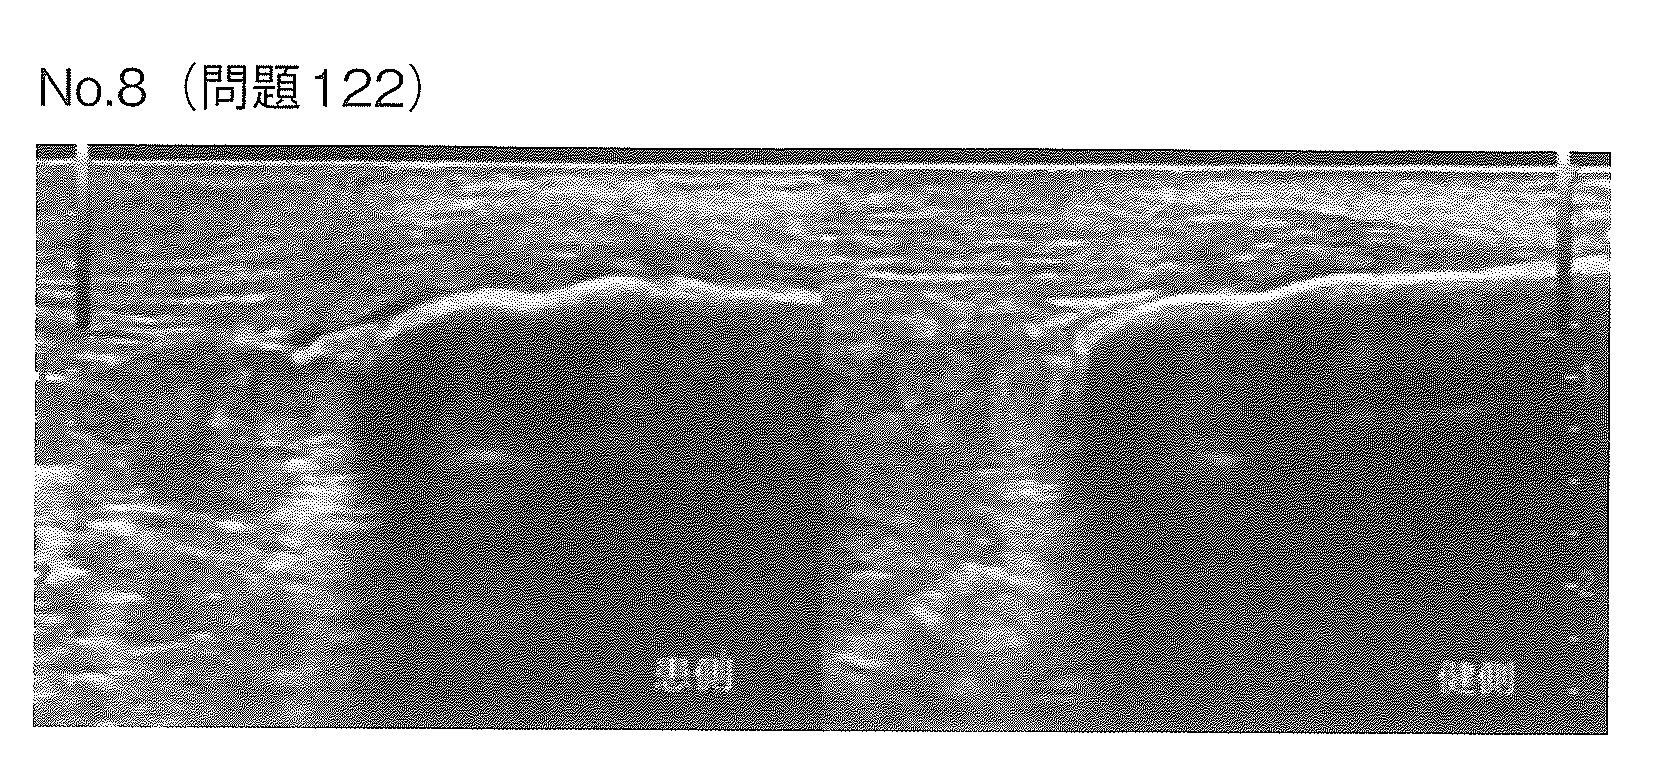

19歳男性。大学で野球部に所属している。入部後練習量が増え、ランニング後にアキレス腱部の痛みが生じる様になったため来所した。長軸超音波画像(別冊No.8)を別に示す。正しい画像所見はどれか。

2→これはアキレス腱炎・周囲炎の典型的な所見であり、炎症により腱が腫脹している状態です。